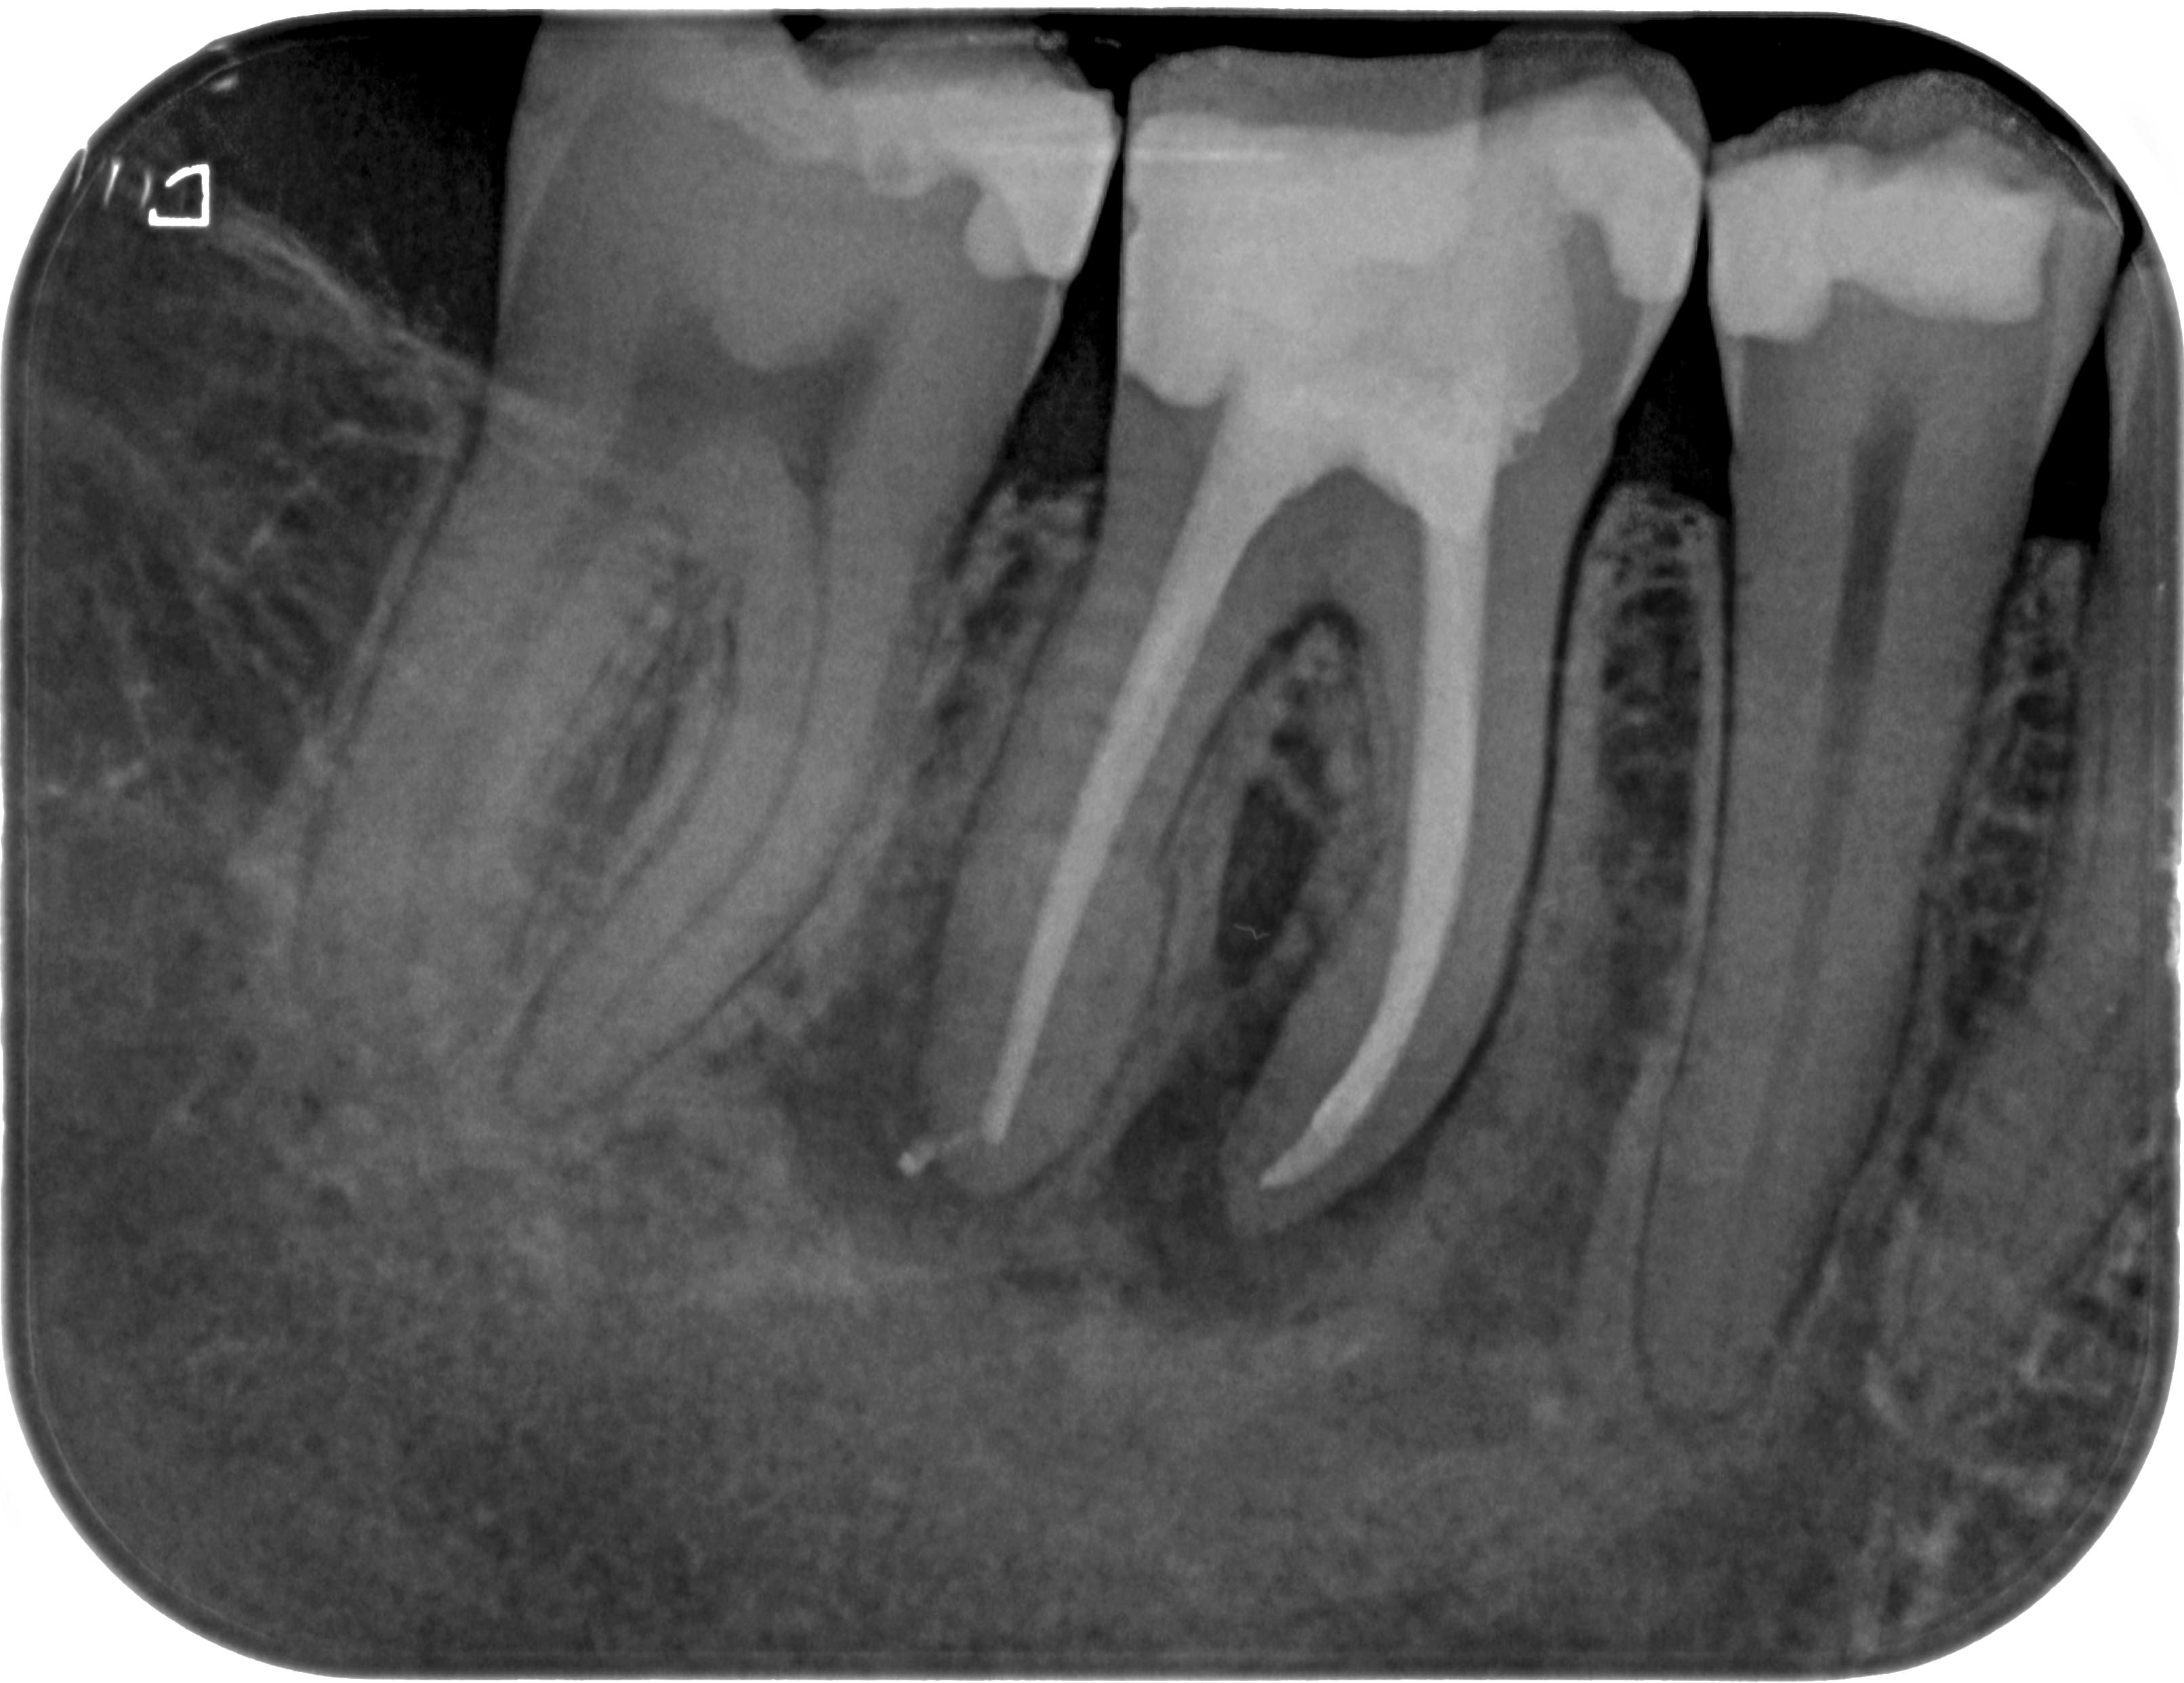

WS46 (2 von 4) Veröffentlicht 21. März 2016 am 3223 × 2483 in Calciumhydroxid- Überpressung (2) 26. Juni 2012